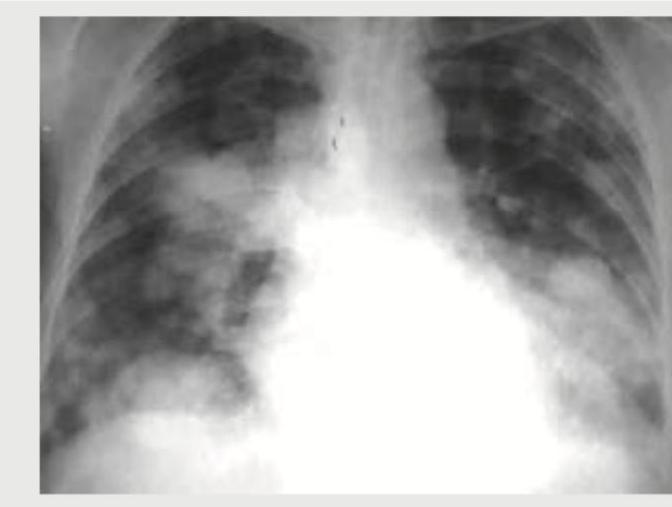

A breast cancer patient presents with difficulty in breathing. CXR shows:

Explanation: ***Cannonball metastasis*** - The chest X-ray shows multiple, well-defined, rounded opacities of varying sizes scattered throughout both lung fields, consistent with the characteristic appearance of **cannonball metastases**. - Given the patient's history of **breast cancer** and new onset **dyspnea**, pulmonary metastases are a very likely cause. *Pneumothorax* - A pneumothorax would appear as an area of translucency with absence of lung markings, often accompanied by a visible visceral pleural line and tracheal deviation in severe cases. This is not observed here; instead, the lungs are filled with multiple lesions. - The image does not show any signs of a collapsed lung, air in the pleural space, or shifted mediastinum. *Pulmonary artery hypertension* - Pulmonary artery hypertension on CXR might show **enlarged central pulmonary arteries** and pruning of peripheral vessels, or signs of right heart enlargement. - The predominant features in this image are numerous discrete nodules, not signs of vascular dilation or heart changes. *Interstitial lung disease* - Interstitial lung disease typically presents with a **reticular, nodular, or reticulonodular pattern**, often with reduced lung volumes and honeycombing in advanced stages. - The distinct, large, spherical lesions seen here are not characteristic of the diffuse, fine patterns associated with most interstitial lung diseases.